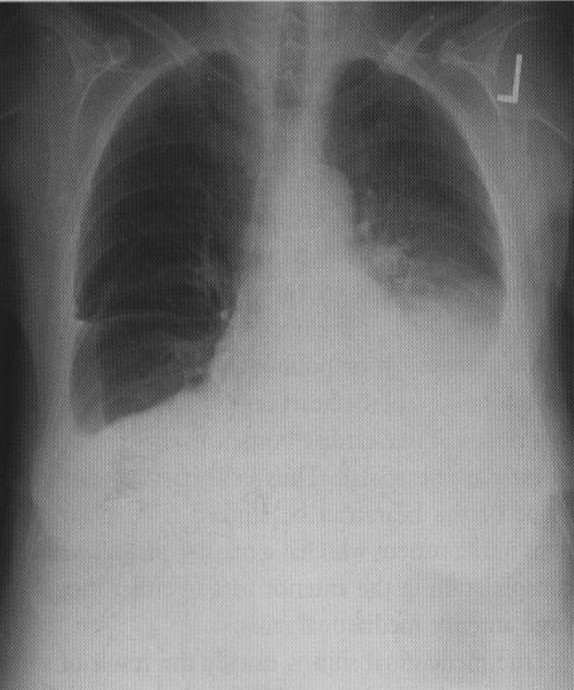

60yo female with history of congestive heart failure presents to the clinic with a 3 week history of worsening SOB

View

DX

DX: pleura effusion